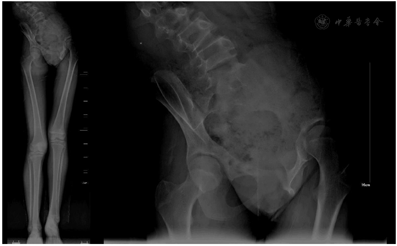

辅助检查:生化全套示碱性磷酸酶为201.8 U/L(参考范围47~185 U/L),总蛋白为60.6 g/L(参考范围65~85 g/L),白蛋白为39.1 g/L(参考范围40~55 g/L),尿素为2.8 mmol/L(参考范围2.9~7.5 mmol/L),肌酐为26 µmol/L(参考范围44~106 µmol/L),总二氧化碳19.9 mmol/L(参考范围22~32 mmol/L),L-胆固醇1.84 mmol/L(参考范围1.89~3.10 mmol/L),载脂蛋白A I为0.85 g/L(参考范围1.00~2.05 g/L),载脂蛋白B为0.56 g/L(参考范围0.6~1.2 g/L)其余正常;肌酸激酶MB同工酶为20 U/L(参考范围1~18 U/L);凝血五项示活化部分凝血活酶时间为35.6 s(参考范围25.0~31.3 s),其余正常。全脊柱普放X线摄影(图1)示脊柱呈明显"S"型弯曲,以胸椎为中心,两侧肋骨12对,未见明显骨性异常,肋间肌尚可,脊柱椎体形态大致正常,未见明显椎体骨性异常,各椎体间隙未见明显异常改变,脊柱侧凸畸形(Cobb角96°,SVA 2.9 cm,冠状面平衡偏离4.8 cm)。立位全下肢X线摄影(图2)示双下肢不等长,骨盆左倾(骨盆倾斜角20°)。